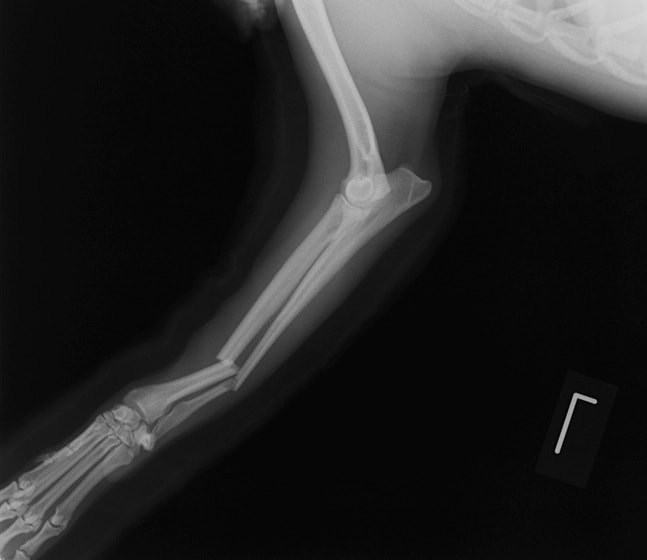

症例3:キルシュナーワイヤーのピンニングによる整復

ペルシャ猫 11ヶ月齢 雄

他院にて左大腿骨遠位の成長板骨折(salter-harrisⅠ型)が認められており、治療相談を目的として来院。当院にて、キルシュナーワイヤーを用いたピンニングにより骨折部位の整復を行いました。術後の経過は良好で、現在も経過観察中です。

術前レントゲン

術後レントゲン